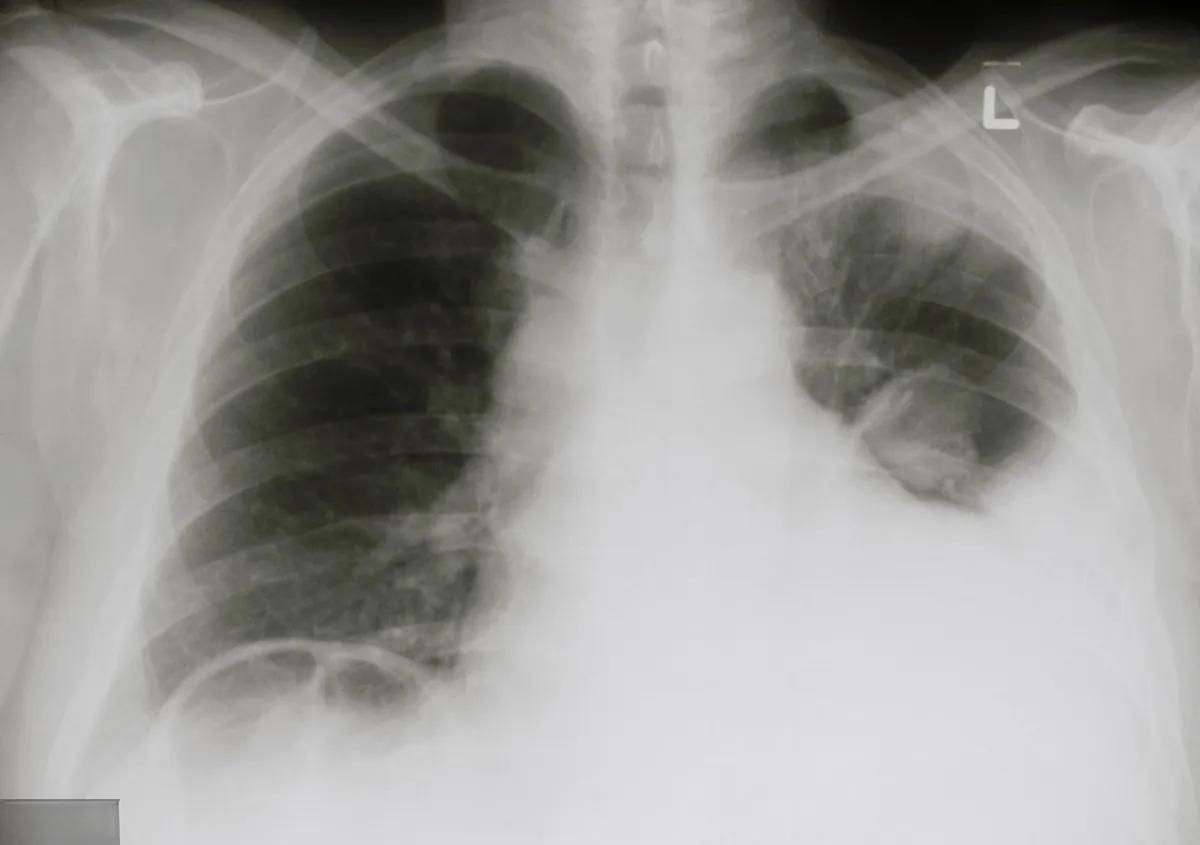

肺生水并不等同于癌症。肺生水,医学上称为肺水肿,是一种常见的呼吸系统疾病,其特征是肺部积聚过多液体。这种病症可能由多种原因引起,而不仅仅是癌症。

肺水肿的症状包括呼吸困难、咳嗽、胸痛等。急性肺水肿患者可能会出现极度气短、咳出泡沫状痰液,甚至带血。诊断通常需要进行胸部X线检查、CT扫描、动脉血气检测等。